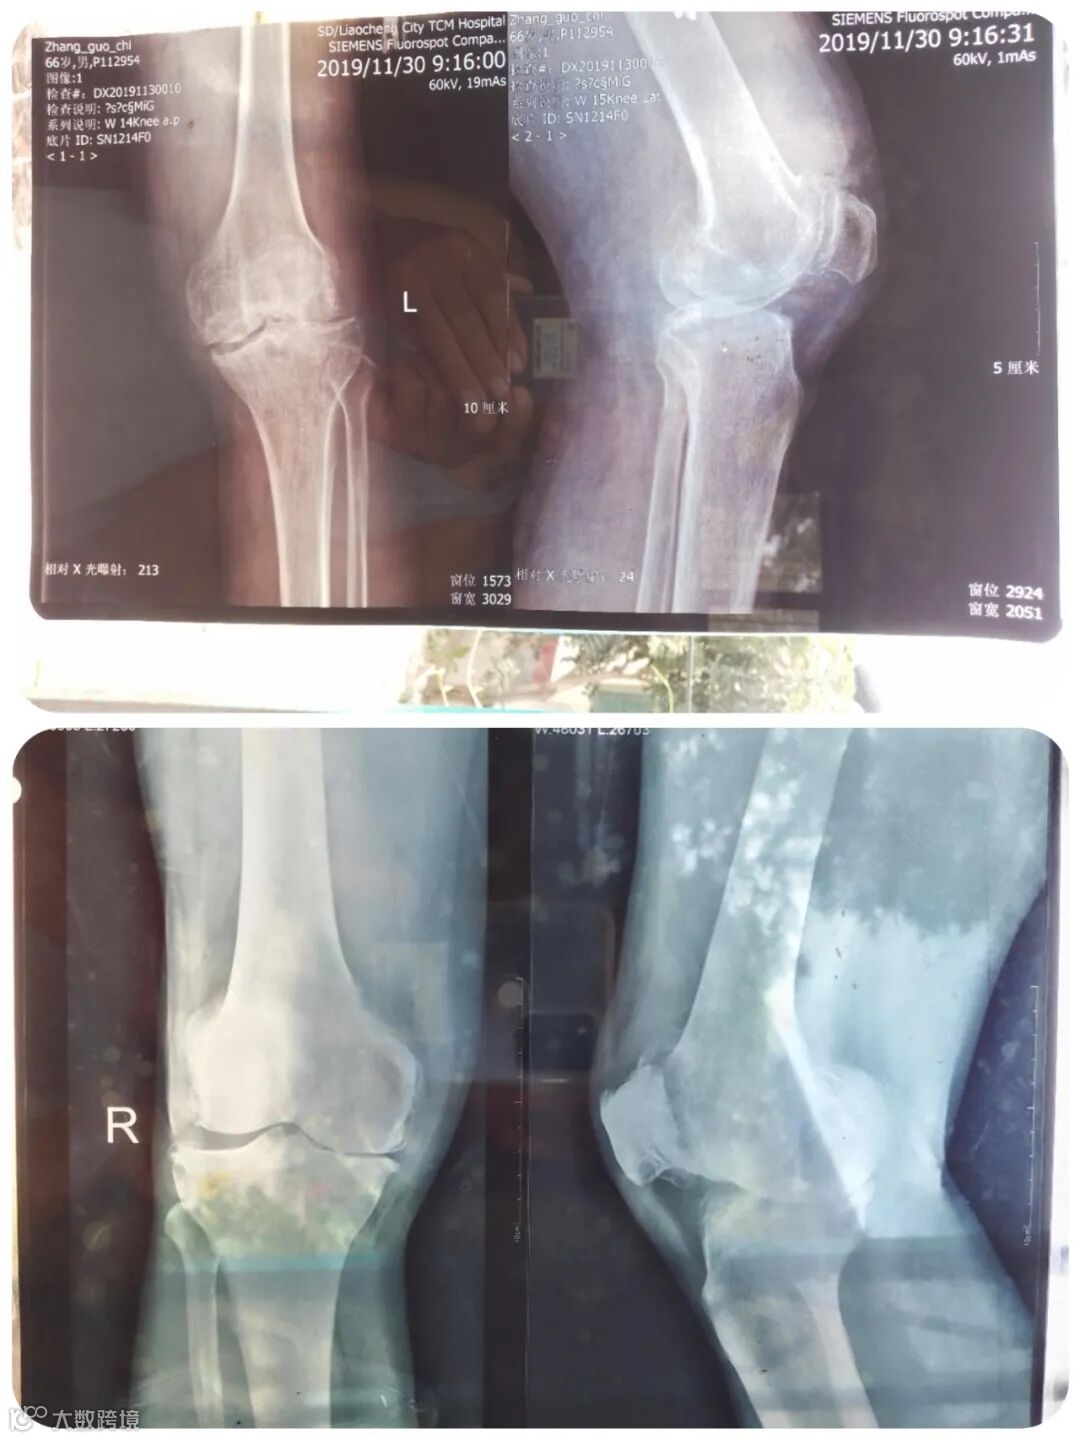

2019年11月30日我又去聊城中医院看病,医生让拍片。看过片子,专家说:膝关节骨头磨骨头是不行的,这软骨垫子(半月板)做什么(治疗)都不会再长了。无论你冷热刺激、药物刺激、吃钙片、做电疗,怎么做都不长了,没有它(半月板)你的腿走不了。看来只有换关节一条路。可是孩子现在没有钱,只能等。儿子说,等两个月后吧!(张国池老人的儿子为超市供货,要等到账期才能结算。)

2019年11月30日,张国池老人在山东聊城中医院的膝关节影像及诊断书